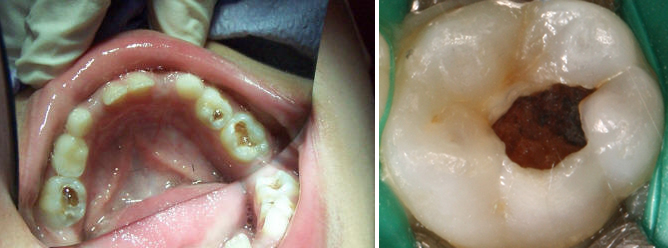

If your infant has no teeth use a clean damp cloth to wipe her gums down after a bottle. In the later stages teeth have brown or black areas. The most common is lack of proper oral hygiene.

At this stage fluoride treatment or placing fluoride varnish. The upper four front baby teeth are most commonly affected. Baby bottle tooth decay also called early childhood caries ECC is the deterioration of a young childs tooth enamel due to prolonged or excessive exposure to sugar or sweetened.

If your baby is experiencing Baby Bottle Tooth Decay treatment is available and effective. 12 to 36 months. White spots on a tooths surface are early symptoms of baby bottle tooth decay according to the North Dakota Department of Health.